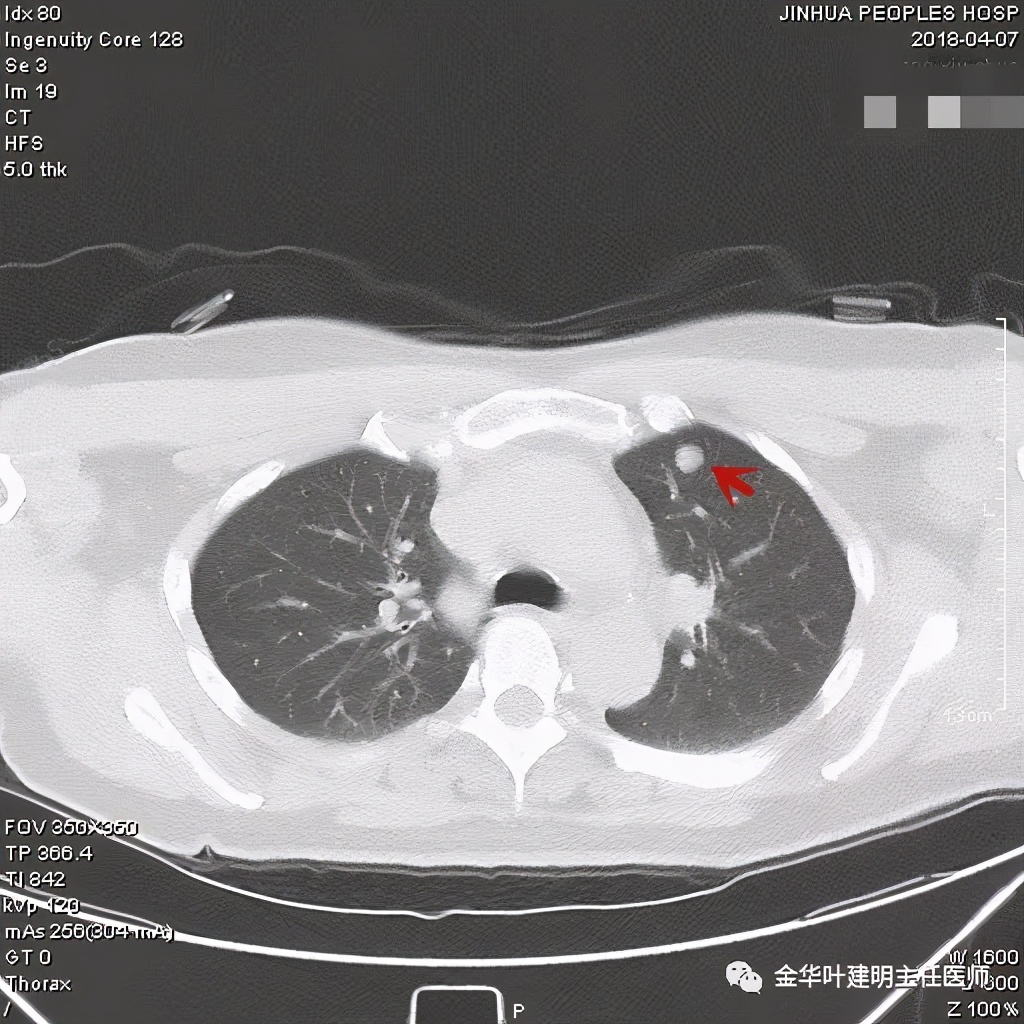

密度非常高的结节,边缘非常光滑

周围,边缘非常光滑,缺乏收缩力

高密度,周围,边缘非常光滑,亚厘米

高密度,边缘非常光滑,周围

这个也比较大,但边缘非常光滑,密度相对较为均匀

其实我们发现,包括今天这例,只要是错构瘤,“边缘非常光滑”是每一像都具备的!虽然有的似有支气管截断、有的似有血管征、有的似有分叶,但总的只要是边缘非常光滑的实性占位,就要想到错构瘤的可能,若有点状钙化密度,更是强烈要考虑。错构瘤如何靠近胸膜,其实可以切开一点肺实质,挤一下,肿瘤就会滚出来。